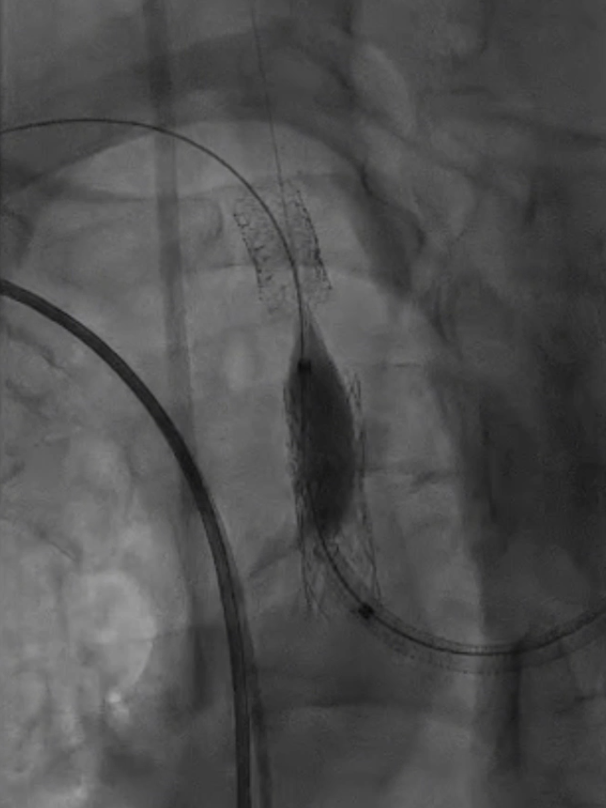

主动脉弓上造影显示无名动脉起始支架内重度狭窄,右椎动脉显影延迟,解除无名动脉支架内狭窄,恢复血流通畅,同时保障脑保护,降低并发症风险。

无名动脉起始支架内重度狭窄右椎动脉显影延迟

球囊扩张:采用同轴双导丝技术,以4×40mm、6×40mm球囊逐级扩张狭窄段;造影发现残存狭窄后,再次用6×40mm球囊扩张。

4*40mm球囊扩张

无名动脉支架

多角度造影

仍有残存狭窄

6*40mm球囊扩张

再次6*40mm球囊扩张